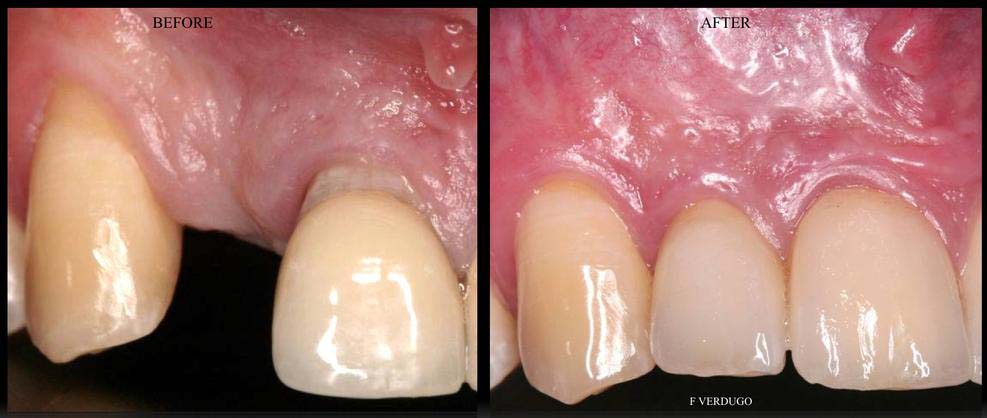

- GUM REGENERATION/GRAFTING FOR RECEDING TISSUES --> GINGIVAL RECESSION THERAPY

- COSMETIC PERIODONTAL PLASTIC SURGERY